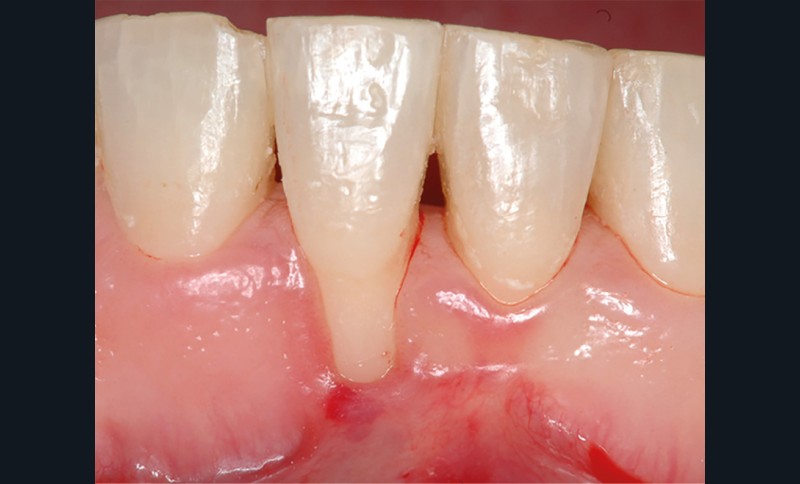

Dans un contexte parodontal sain, le principal facteur de risque à identifier avant un traitement orthodontique est le phénotype parodontal fin. L’examen clinique se réalise à l’aide d’une sonde parodontale graduée. Celle-ci est visible par transparence lors de son insertion dans le sulcus (fig. 1). D’un point de vue clinique, il est important de remarquer qu’il peut exister des différences d’épaisseur et de hauteur des tissus kératinisés (phénotype gingival) en fonction des dents d’un même secteur (fig. 2).